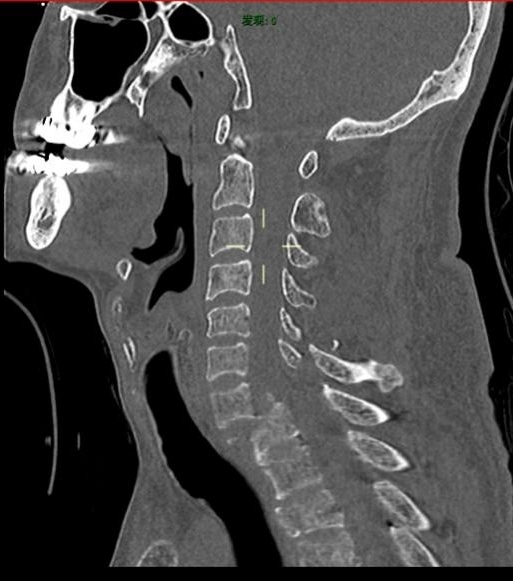

术前MR提示:C7椎体完全脱位,颈胸椎多发骨折

术前颈椎CT